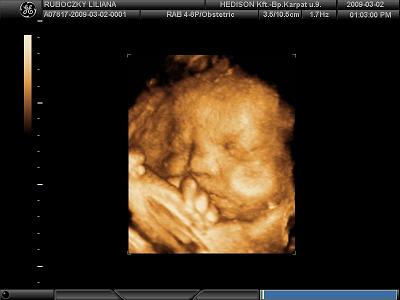

Na ma voltam 4D uh és Sára baba 3300 gr nyom. Nem semmi, és még ugye 1 hónap hátra van.

Kép

De szerintem nem fogom hordani olyan okáig a pocakomban.